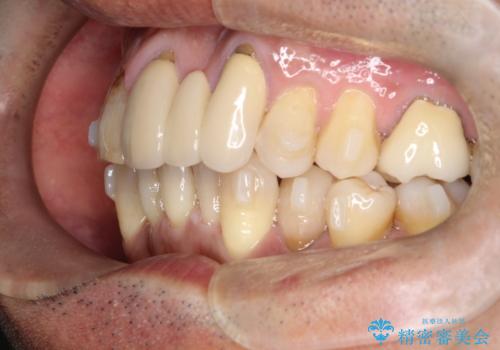

50代からの矯正治療!ブリッジを活かし八重歯を解消

- 50代の患者様で、右上の八重歯と歯並びの乱れを気にされてご来院されました。特に、すでに装着されている前歯のセラミックブリッジを外したくないという強いご希望がありました。精密な検査の結果、八重歯を治すためのスペースが不足しているため、右上の4番目の歯(小臼歯)を抜歯し、そのスペースを利用して歯並び全体を整える治療計画を立案。装置には目立たないインビザラインを採用し、ブリッジを温存しながら八重歯の改善を目指しました。

今回の治療で最も重要だったのは、患者様のご要望通り既存のセラミックブリッジを外さずに矯正を進める点でした。計画通り右上の小臼歯を抜歯し、透明なインビザラインを使用して抜歯スペースを閉じながら、八重歯を正しい位置へ移動させました。ブリッジの形態と調和するに、他の歯の移動を工夫をすることで、複雑な条件をクリア。治療の結果、長年気にされていた八重歯が解消され、見た目が大きく改善しました。50代からでも、ご自身の要望を叶えながら、美しく機能的な歯並びを獲得していただけました。